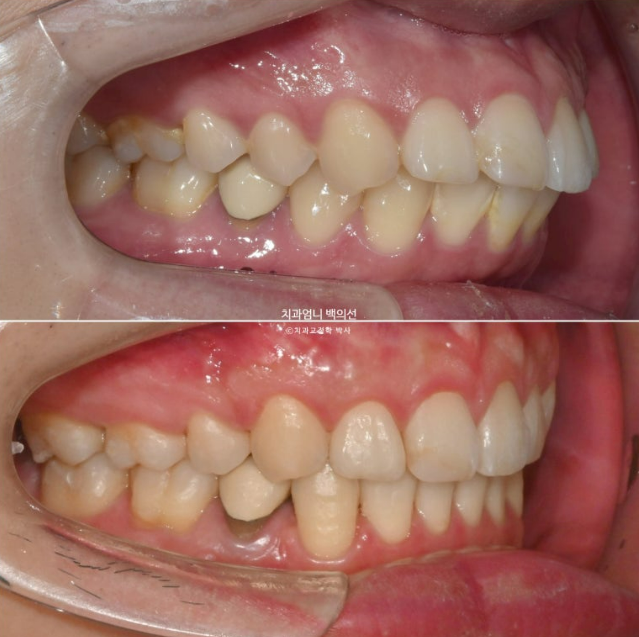

2022.12월 돌출입을 주소로 내원한 환자분 입니다.

앞니 중심선이 어긋나있고 앞니 기울어짐이 보입니다.

2022.12

앞니가 상당히 뻗쳐있는 상태 뻗침과 돌출이 심해서 입이 잘 안다물어지는 상태였고 골격분선상 골격성 2급 부정교합 (무턱)도 있습니다.

2022.12~2025.05

발치공간은 깔끔하게 마무리 되었습니다.

중심선과 캔팅의 개선